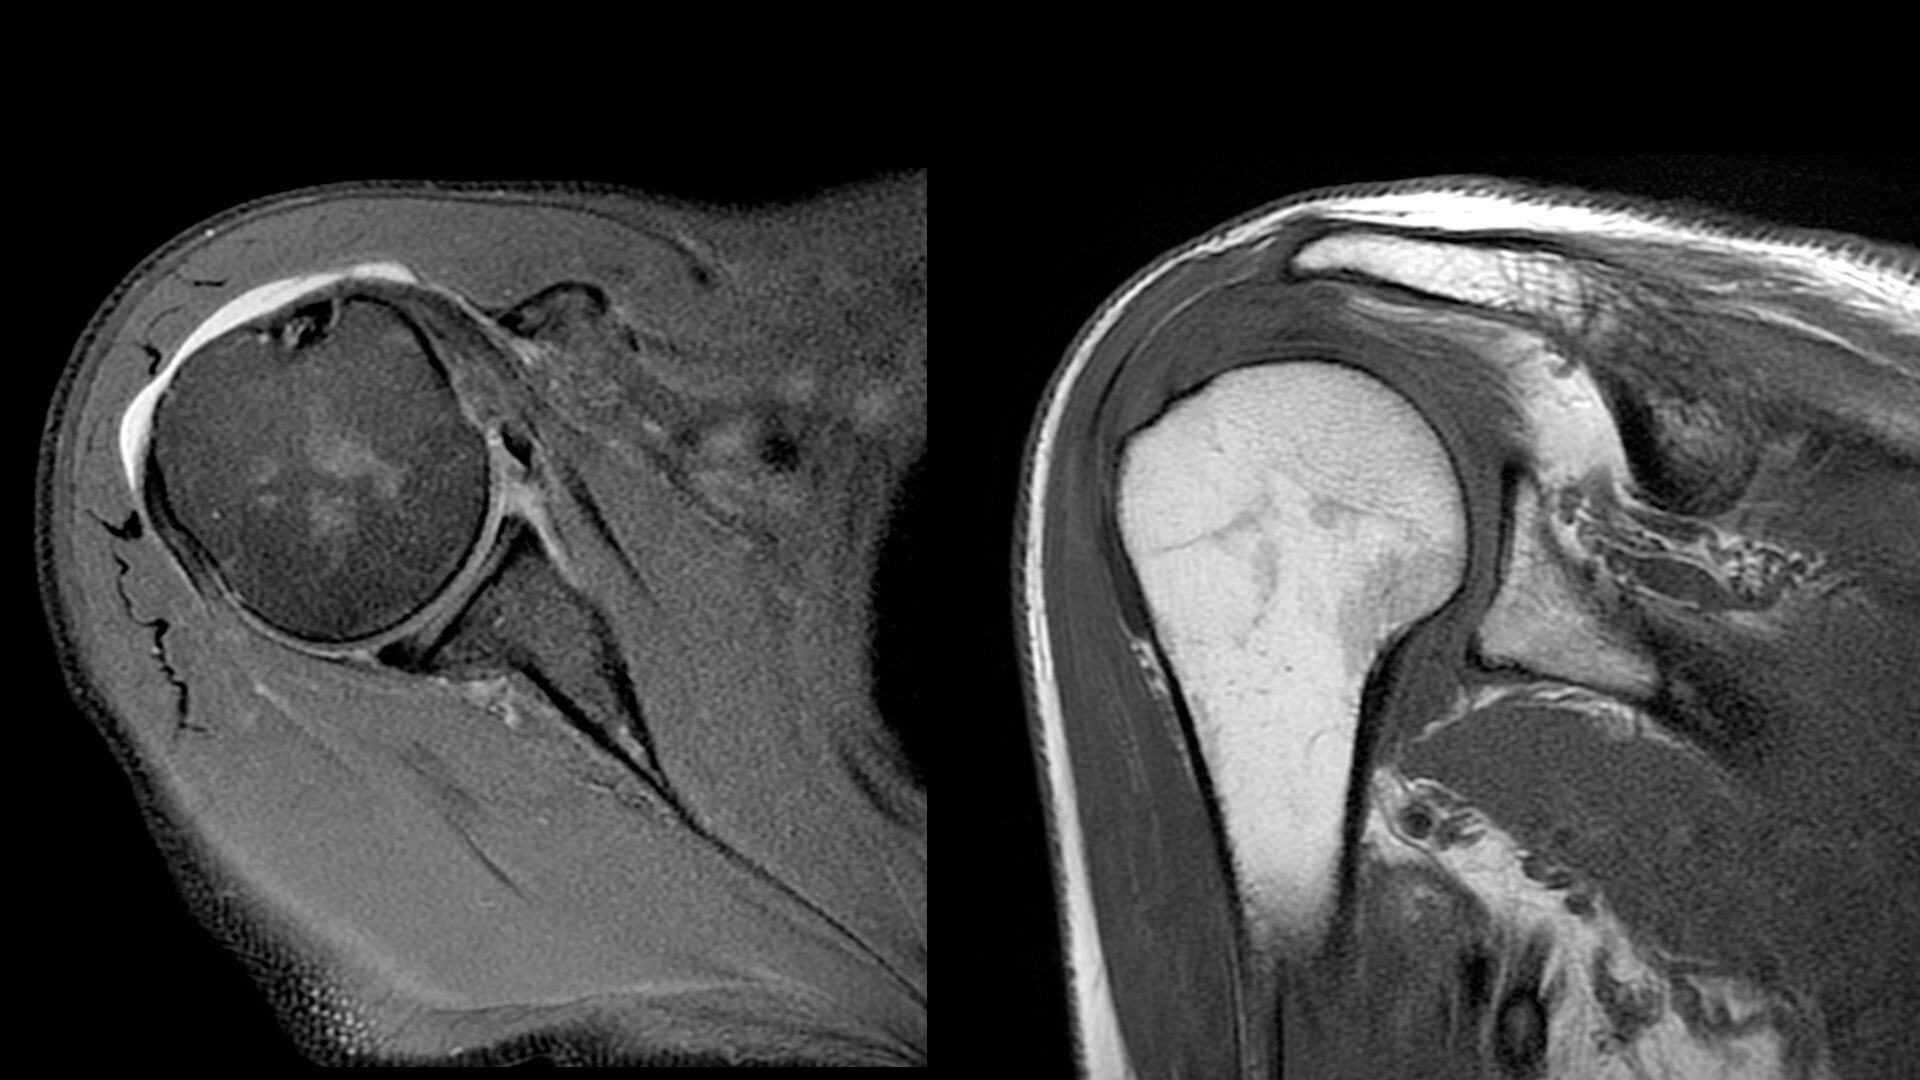

The shape of the MRI coil no longer determines what you can do with it. Wrap it around a knee for a complete knee image. Drape it over the patient's body. With an adaptive AIR™ Coil that is light, form fitting and easy to position, it’s the closest you can get to total positioning freedom with 360-degree coverage.

• 360 degrees of coverage for MSK imaging

• Positioning freedom with previously hard-to-scan anatomies